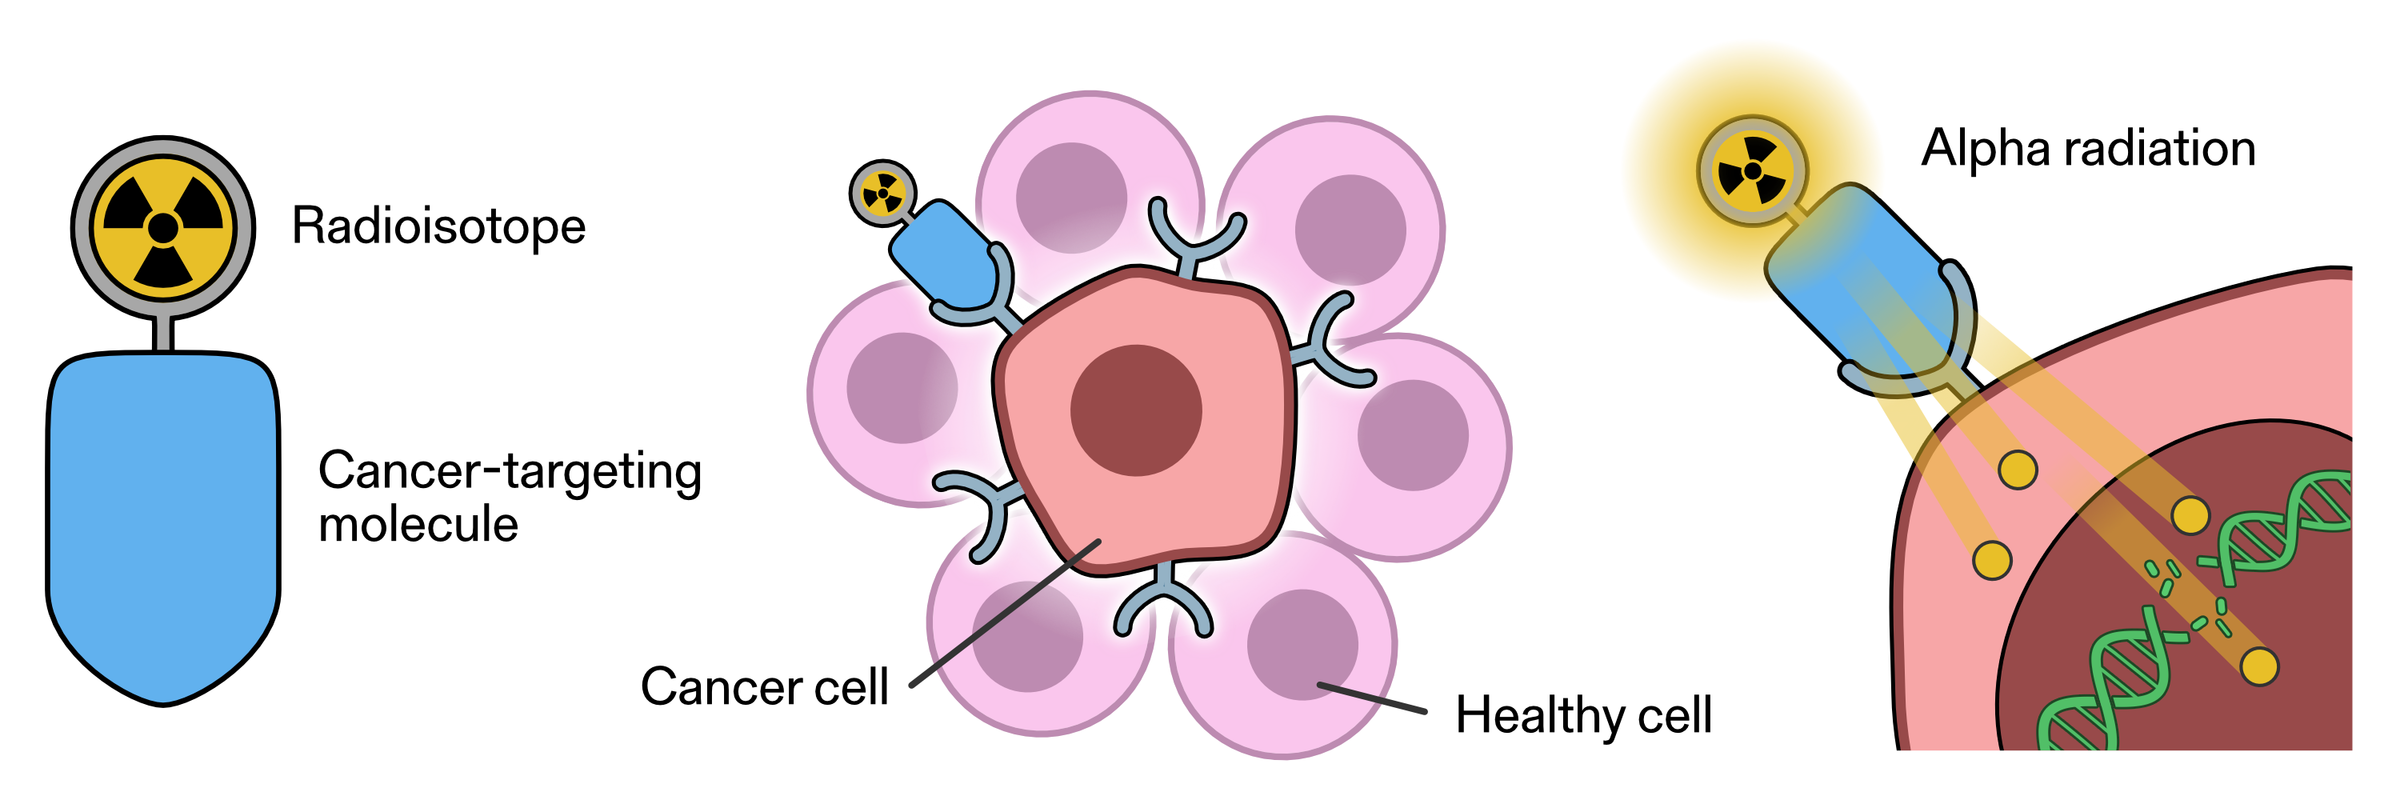

Androgen deprivation therapy (ADT), often referred to as hormonal therapy, is effective in slowing cancer growth among men with prostate cancer; however, maintaining quality of life in tandem with its side effects is important. ADT works by significantly …